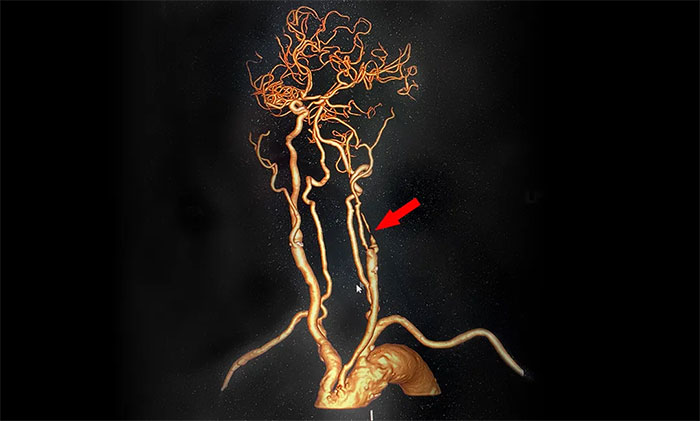

▲ CTA显示,左侧颈内动脉闭塞

脑血管造影显示,左颈总动脉起始段、下段中度狭窄,左颈外动脉起始段重度狭窄,左颈内动脉起始段闭塞,远端颈内动脉缓慢显影至眼动脉;左椎动脉、左大脑后动脉、基底动脉显影,左椎V4段经侧枝向左侧枕动脉代偿供血至左颈外动脉;右颈内动脉起始段轻度狭窄。

术中,超滑导丝、多功能导管经过反复尝试顺利通过左颈内动脉起始段,到达左颈内动脉远端显影段,路图见远端血管通畅,左大脑中动脉显影;随后,微导丝经多功能导管置于左颈内动脉海绵窦段,经微导丝送入保护伞至左颈内动脉岩骨垂直段并释放,再沿保护伞微导丝送入4x30mm球囊于左颈内动脉起始段,给予球囊扩张,撤除球囊后造影见左颈内动脉起始段再通,左颈内动脉、左大脑中动脉显影;最后,送入9x50mm支架,释放于左颈内动脉颈段至左颈总动脉末段,造影见左颈内动脉起始段显影明显改善,左颈内动脉、左大脑中动脉、左大脑前动脉显影可,行3D造影见左颈内动脉颈段显影改善。行支架CT见支架成形可,行XperCT未见颅内出血。